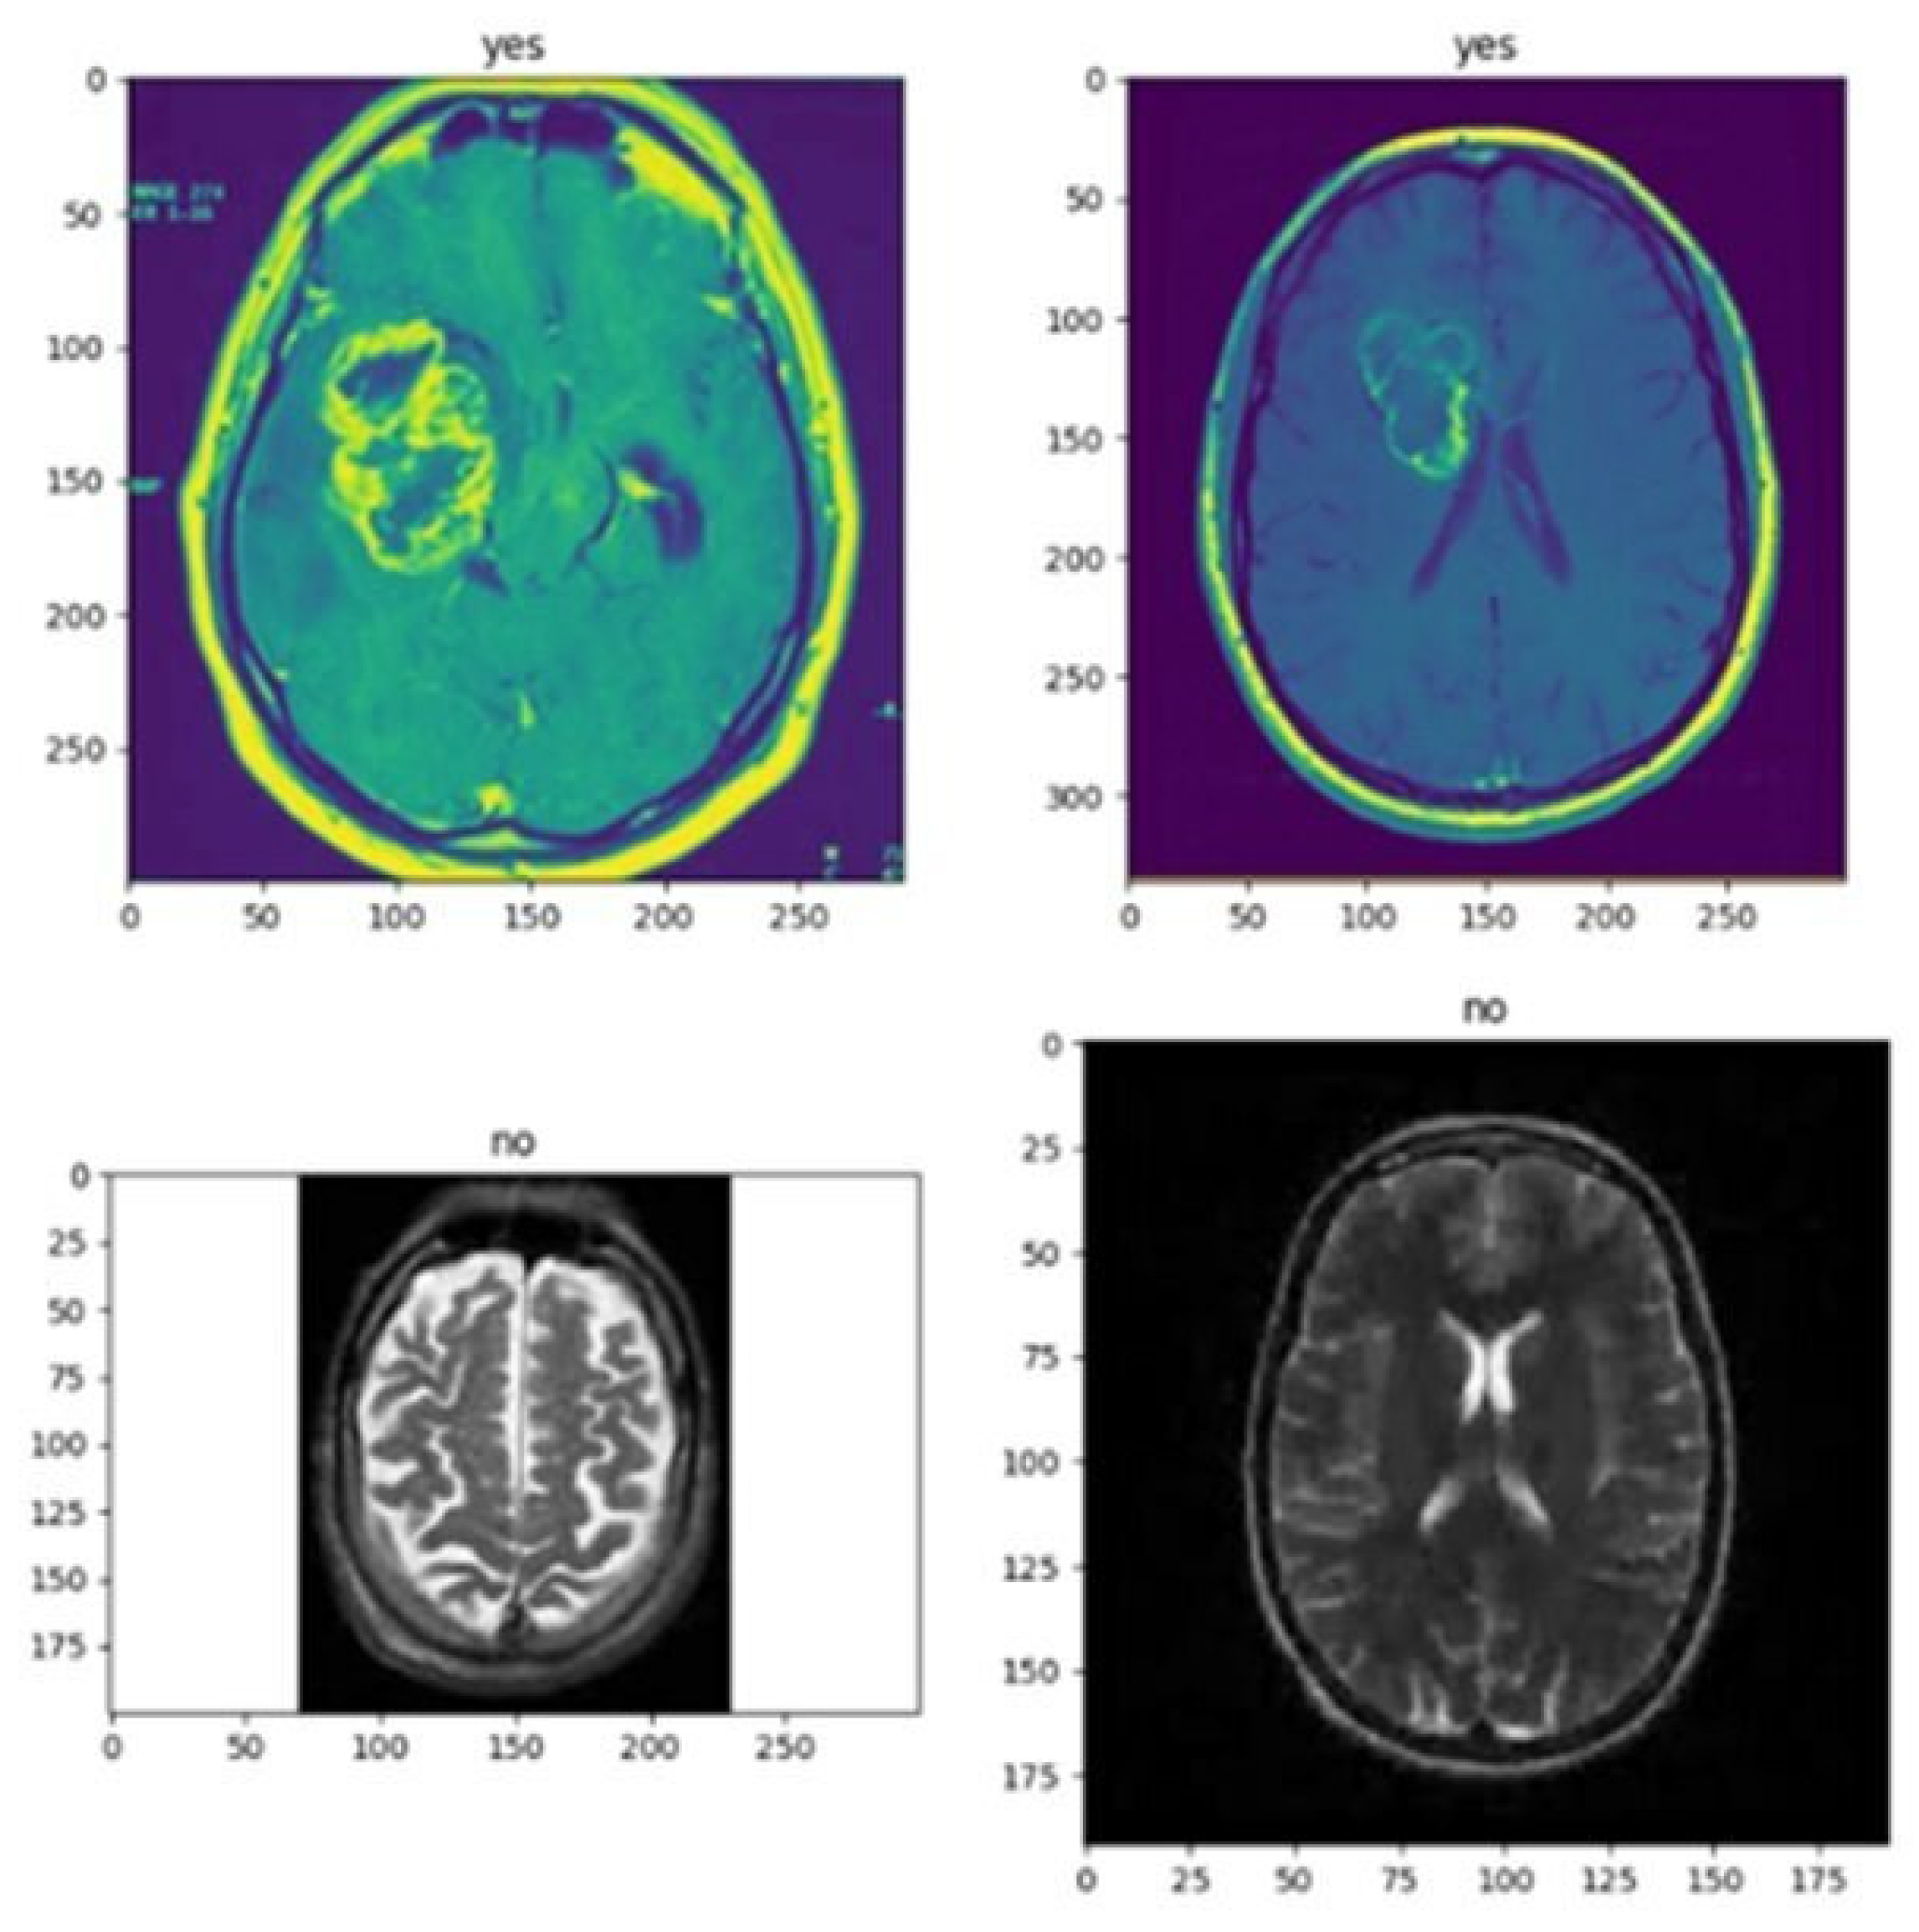

- Pre-Processing: The methods used to obtain digital images ready for examination or additional processing are referred to as image pre-processing. Enhancing the clarity or quality of the image and making it simpler to retrieve valuable information from it are the two main objectives of image pre-processing.

- Feature Extraction and Selection: Selecting a portion of the most significant characteristics from a dataset’s larger collection of features is known as feature selection. This is usually accomplished by selecting the characteristics that are most informative for the model after assessing each feature’s correlation or significance with respect to the target variable. Contrarily, feature reduction entails condensing the initial collection of features into a new set that is smaller and yet preserves the majority of the original features’ content.

- Image Classification: In computer vision, classifying images is a frequent activity that entails labeling a picture according to its visual information. Image classification aims to create a model that can correctly recognize the objects or scenes that are seen in an image and give the image the appropriate label or labels.